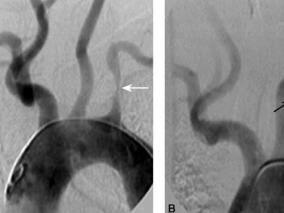

1小时条评论1 病例简介 患者女,62岁,因反复发作性眩晕1个月于2009年11月14日入我院神经内科。近1个月开始出现反复发作性头晕,每2~3天发作1次,每次持续5分钟左右,伴视物旋转,无恶心、呕吐,上肢活动后头晕无加重,无肢体活动障碍,与转颈和头位改变无关,遂再次入院。 ...